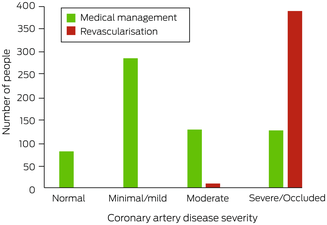

Eighty of the 1017 people who underwent ICA had no coronary artery stenosis (7.9%), 285 had minimal or mild CAD (28.0%), 137 had moderate CAD (13.5%), and 515 had severe CAD or an occluded vessel (50.7%) (Box 4). A larger proportion of people with NSTEMI had obstructive CAD (≥ 50% stenosis) than of those with alternative indications for ICA (327 of 438 [74.7%] v 325 of 579 [56.1%]; OR, 2.3; 95% CI, 1.8–3.0).

Coronary artery disease: management

After undergoing ICA, 619 people were medically managed (60.9%) and 398 underwent revascularisation (39.1%; ICA:revascularisation ratio, 2.6). No‐one with non‐obstructive CAD (< 50% stenosis), nine with moderate CAD (7%), and 389 with severe CAD or an occluded vessel (75.5%) underwent revascularisation (Box 5). A larger proportion of people with NSTEMI underwent revascularisation (55%) than of those with chest pain and normal troponin levels (35%; OR, 2.3; 95% CI, 1.7–3.0) or other indications for ICA (10%; OR, 11; 95% CI, 6.4–18) (Box 6). Twenty‐three people experienced peri‐procedural complications (2.3%) (, table 3).

We report the first study of CAD severity in people in rural and remote locations of WA referred with non‐urgent indications to metropolitan tertiary hospitals for ICA evaluation. More than one‐third of people in the study had normal coronary arteries or non‐obstructive CAD (< 50% stenosis), all of whom were medically managed. About 75% of people with severe CAD or an occluded vessel underwent revascularisation (389 of 515), but only 7% (nine of 137) with moderate CAD (50–69% stenosis); in total, for every 2.6 ICA assessments undertaken, one patient underwent revascularisation. We also found that undertaking CTCA in rural centres could avert 53% of transfers for ICA by locally identifying people with non‐obstructive CAD who may not require ICA. This would reduce the number of required metropolitan hospital bed‐days by 43%, health care costs by 36%, the ICA:revascularisation ratio from 2.6 to 1.6, and lost productivity by three days per patient.

Box 5 – Management of 1017 people from rural or remote Western Australia who underwent invasive coronary angiography in Perth during 2019, by severity of coronary artery disease

Box 6 – Management outcomes of 1017 people from rural or remote Western Australia who underwent invasive coronary angiography in Perth during 2019, by indication for referral